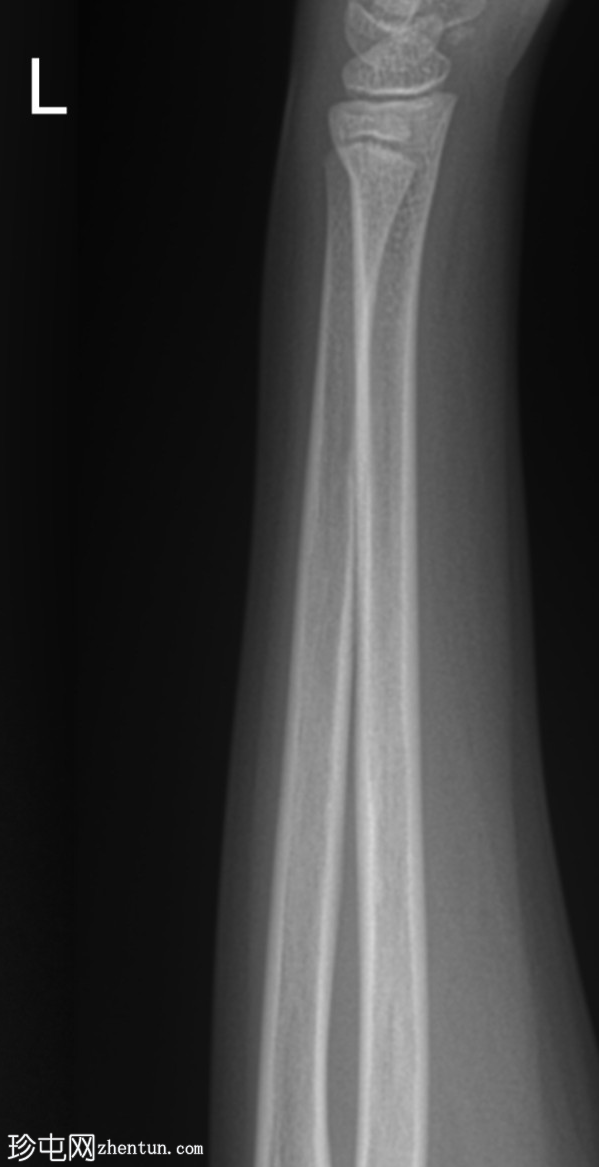

侧位片

桡骨远端干骺端皮质骨隆起,符合骨性骨折(Cuckle fracture)的特征。

骨性骨折(Cuckle fracture)是指长骨干的不完全性骨折,其特征是皮质骨隆起;常见于儿童,常累及桡骨远端干骺端。